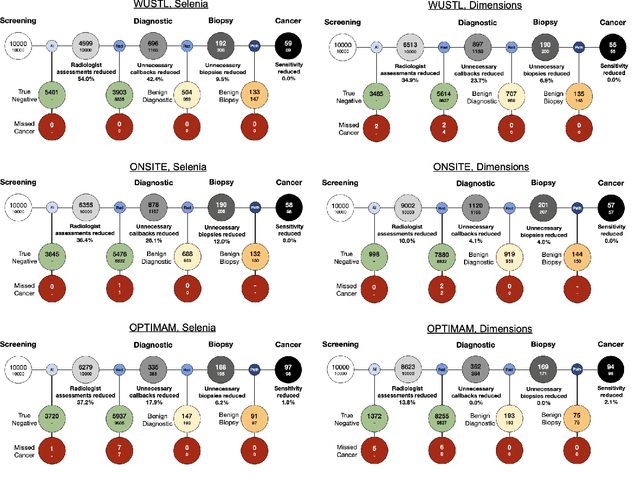

Screening mammography improves breast cancer outcomes by enabling early detection and treatment. However, false positive callbacks for additional imaging from screening exams cause unnecessary procedures, patient anxiety, and financial burden. This work demonstrates an AI algorithm that reduces false positives by identifying mammograms not suspicious for breast cancer. We trained the algorithm to determine the absence of cancer using 123,248 2D digital mammograms (6,161 cancers) and performed a retrospective study on 14,831 screening exams (1,026 cancers) from 15 US and 3 UK sites. Retrospective evaluation of the algorithm on the largest of the US sites (11,592 mammograms, 101 cancers) a) left the cancer detection rate unaffected (p=0.02, non-inferiority margin 0.25 cancers per 1000 exams), b) reduced callbacks for diagnostic exams by 31.1% compared to standard clinical readings, c) reduced benign needle biopsies by 7.4%, and d) reduced screening exams requiring radiologist interpretation by 41.6% in the simulated clinical workflow. This work lays the foundation for semi-autonomous breast cancer screening systems that could benefit patients and healthcare systems by reducing false positives, unnecessary procedures, patient anxiety, and expenses.